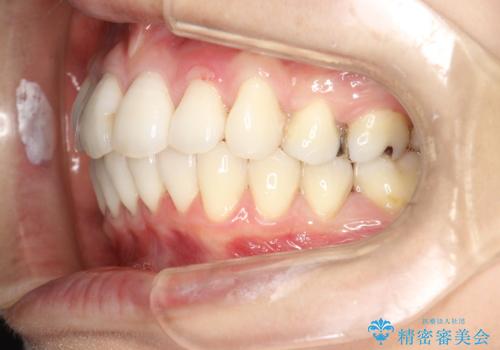

裏側のワイヤー矯正 抜歯して前歯をしっかり後ろに下げる

- 出っ歯が気になるとのことで来院されました。

上顎の、前から4番目の歯を左右1本ずつ抜歯して前歯を後方に下げる計画としました。

目立たずに矯正をご希望でしたので、裏側矯正で治療を行いました。

上下裏側矯正であったため、舌に傷や口内炎ができるなどつらい経験もされましたが、目立たずに治療できたことに喜んでいただけました。